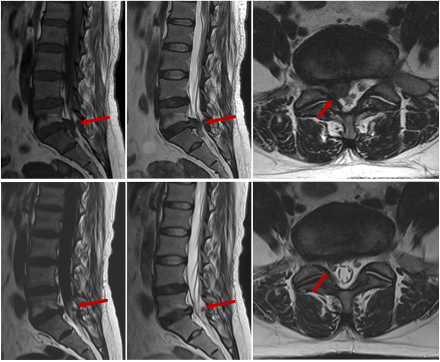

目前,腰椎间盘突出症的治疗策略分为手术治疗和保守治疗。保守治疗是大多数新诊断的腰椎间盘突出症患者的首选。常规疗程至少为6周,主要形式包括卧床休息、药物治疗、康复治疗、硬膜外注射、腰椎牵引和中医治疗。大多数腰椎间盘突出症症状可以通过保守治疗缓解。此外,通过MRI和计算机断层扫描(CT)等影像学检查,一些患者的椎间盘突出部分缩小甚至消失。临床上,未经手术干预的腰椎椎间盘自发收缩或消失的现象称为重吸收。腰椎间盘突出症的自发重吸收已成为广泛认可的临床观察。